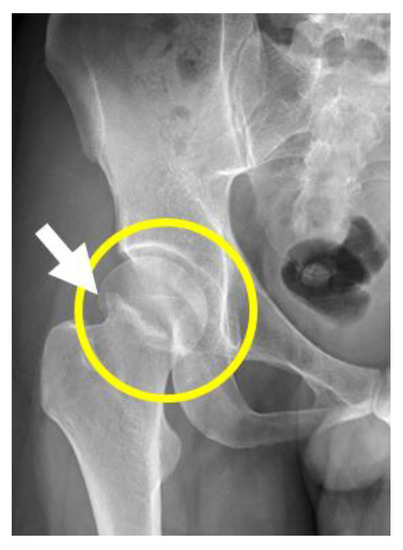

2. Case Presentation